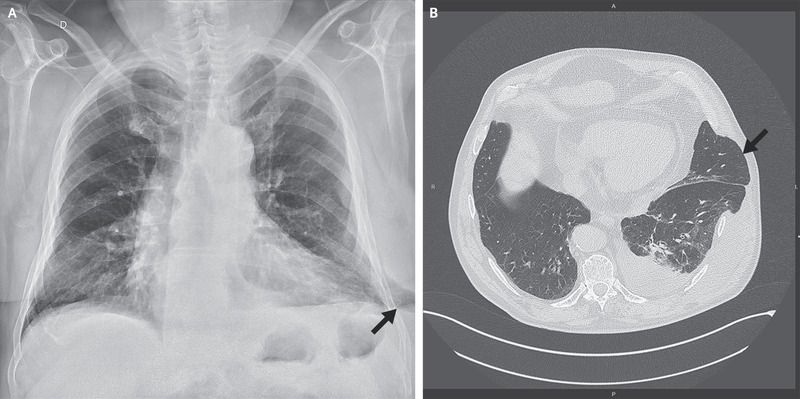

A radiograph of the chest showed extension of lung parenchyma beyond the rib cage laterally at the base of the left lung (Panel A, arrow). Computed tomography of the chest revealed lung herniation through a left lower intercostal space laterally, as well as a moderate pleural effusion on the left side (Panel B, arrow). The patient underwent successful surgical repair of the hernia.